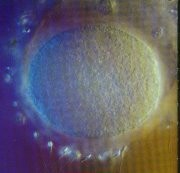

卵子經過大約15釐米長的、狹窄的輸卵管向子宮遊動,它周圍的營養細胞像一串串美麗的光環圍繞著它。很快,它將與精子相遇並開始受精的過程。